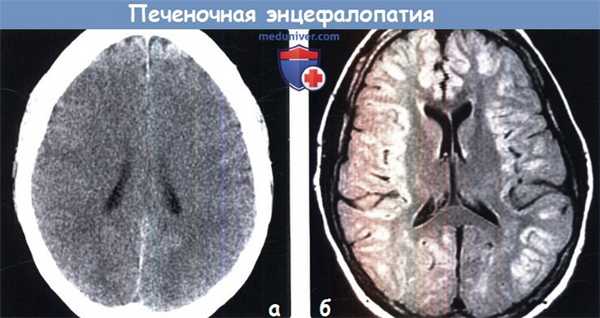

2. КТ признаки печеночной энцефалопатии:

• Бесконтрастная КТ:

о ОПЭ: выраженный диффузный отек большого мозга

о ХПЭ: атрофия большого мозга

(а) Бесконтрастная КТ, аксиальный срез: у пациента с острой печеночной энцефалопатией отмечается диффузный отек большого мозга, проявляющийся потерей дифференцировки серого и белого вещества и облитерацией борозд.

(б) МРТ, FAIR, аксиальный срез: у пациента с острой печеночной энцефалопатией определяется диффузное повышение интенсивности сигнала от коры с относительной сохранностью затылочных долей.